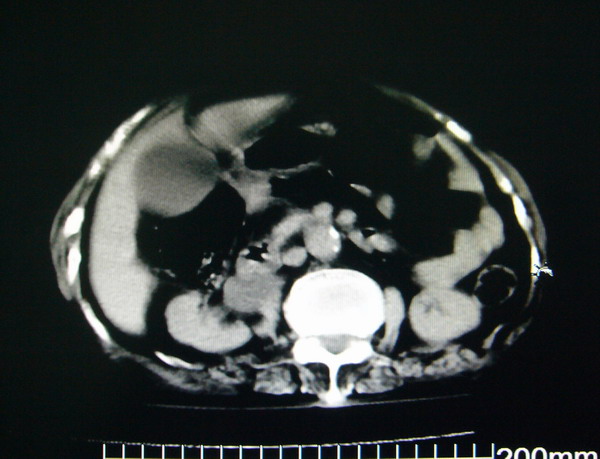

女:83y,转移性右下腹痛2小时,白细胞计数增高。

1.右侧肾盂扩大,肾盏无扩张,考虑:先天性肾盂变异可能性大。

2.胆囊扩张,考虑:胆囊炎。

3.阑尾区域可见以结节样高密度影,结合病史,考虑:阑尾结石,阑尾炎。

右下腹肠系膜增厚,结合病史支持阑尾炎.

右侧壶腹型肾盂可能,建议输路造影或增强

1.右侧肾盂扩大,考虑先天性肾盂变异或肾盂旁囊肿。

2.胆囊扩张,考虑胆囊炎。

3.阑尾区域可见结节样高密度影,结合病史考虑:阑尾结石、阑尾炎。